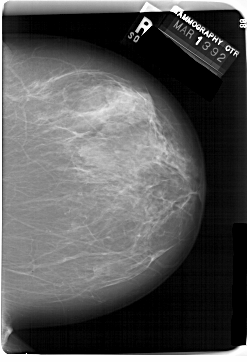

A_1466_1.RIGHT_MLO

RIGHT_CC LINES 6871 PIXELS_PER_LINE 4681 BITS_PER_PIXEL 12 RESOLUTION 43.5 NON_OVERLAY